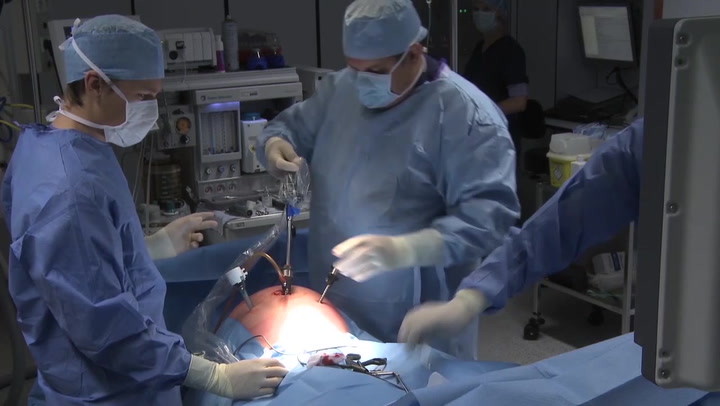

Tim Tollens, M.D. | HerniaU live Inguinal TAPP procedure

The session kicks off with Dr. Tollens and his team from Belgium discussing a patient's case history, including previous surgeries and current condition. [...]